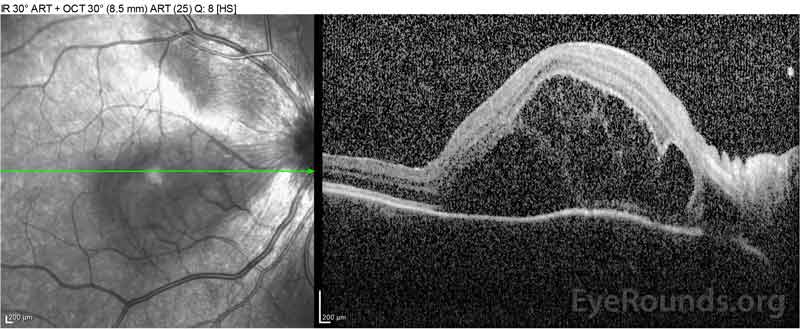

Figure 2: Optical coherence tomography (OCT) of the right eye (upper panels) shows a serous retinal detachment involving the fovea with extensive overlying intraretinal fluid, disruption of the outer retinal layers, and undulations of the thickened choroid. OCT of the left eye (bottom panels) shows a serous retinal detachment in the nasal macula extending up to the fovea.

Figure 4: Optical coherence tomography showing subretinal fluid at baseline (top) and the course of resolution at one week (middle) and five weeks (bottom) while on a high-dose oral prednisone taper. Note the smoothing out of the choroidal undulations with treatment.